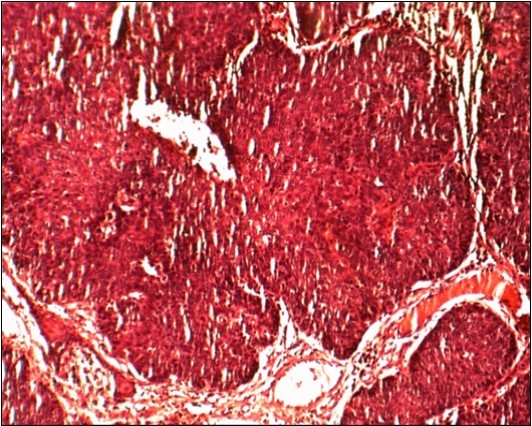

All 23 patients presented invasive differentiated squamous cell carcinoma (Figure 3). None in situ carcinoma was found.

Figure 3.Imature Squamous cell carcinoma ,Hématein Eosin Coloration (HEX100):Epideremoid growth pattern without kératization

Imature Squamous cell carcinoma ,Hématein Eosin Coloration (HEX100):Epideremoid growth pattern without kératization